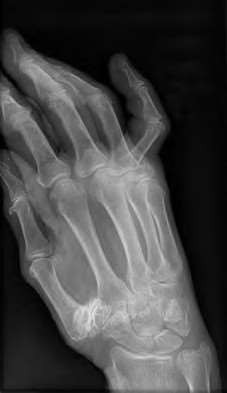

A 35-year-old woman reports wrist pain after a fall onto an outstretched hand. On exam, she has focal tenderness over the wrist snuffbox. A radiograph and CT image are shown in Figures A and B. What is the proper treatment of her injury?

Contrast enhanced MRA of the wrist is typically used to diagnose hypothenar hammer syndrome or other vascular abnormalities.